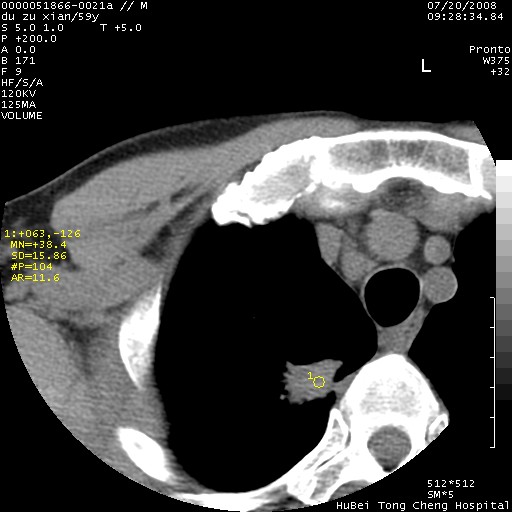

以下是引用宇宙ct在2008-8-25 23:21:00的发言:[br]右肺周围性肺癌并肋骨转移,纵隔淋巴结转移。

以下是引用zsl6918在2008-8-25 22:40:00的发言:[br]右肺周围性肺癌并肋骨转移,纵隔淋巴结转移。

以下是引用zy_zj在2008-8-26 15:24:00的发言:[br]单从病变本身,我倾向良性炎性病变,但肋骨转移了,所以说是考虑右肺周围性肺癌并肋骨、纵隔淋巴结转移可能性大。